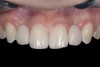

(1.) Initial presentation. Note midline shift to right, missing right lateral incisor, and diminutive left lateral incisor in crossbite.

Figure 1

A 14-year-old patient presented to the office with his mother (Figure 1). His chief complaint involved the large spaces between the teeth created by his missing right maxillary lateral incisor and his small left maxillary lateral incisor. He desired to replace the missing tooth with an implant and create a beautiful smile. Upon examination, he was found to have a class I canine and molar relationship, but because he had a tooth size/arch size discrepancy and space distal to the right central incisor, the remaining incisors had drifted to the right. The left maxillary lateral incisor was peg-shaped and in a cross bite position. Studies have shown a clear association between congenitally missing teeth and reduced tooth size.59-62 Because he was only 14-years-old at the time and could not have implants placed until the cessation of growth (somewhere in the vicinity of 22 years old), he was sent to the orthodontist for alignment of the teeth.16,17 After 2 years of orthodontics, the appliances were removed, and his tooth coloration was improved using carbamide peroxide bleaching (Figure 2). Because some form of provisional needed to be placed until he was finished growing, a double-wing metal resin-bonded bridge was chosen. As discussed earlier, this is the ideal transitional prosthesis for patients that have congenitally missing maxillary lateral incisors. The benefits of this type of prosthesis include its ability to be removed and rebonded during the surgical phase of treatment and its ability to retain the roots in their proper position after orthodontic treatment.16 The final plan for the patient was to increase the width of the central and the maxillary left lateral incisor, utilizing porcelain laminate veneers to achieve the appropriate width/length ratio of 80%. A wax-up was created to idealize tooth size, a putty matrix was made from the wax-up to facilitate bonding of the incisors, and a non-precious, double-wing metal resin-bonded bridge was fabricated for lateral incisor replacement. Once the teeth were bonded to ideal size, the “Maryland Bridge” was fabricated from a polyvinyl arch impression with the newly bonded teeth (Figure 3). The metal frame was cast from a non-precious alloy to allow for fabrication of a very thin frame and to create a better surface for bonding. After sandblasting the internal aspect of the frame with CoJet™ silica (3M ESPE), accomplishing salinization, and executing cementation with a dual-cure resin cement, a fairly good adhesion to the frame was anticipated.29 The enamel surface was etched with phosphoric acid for 30 seconds, the primer (Single Bond Plus, 3M ESPE) was applied to both the internal surface of the sandblasted framework and the etched enamel, and the bridge was cemented with RelyX™ ARC (3M Espe) dual-cured resin cement (Figure 4 and Figure 5).